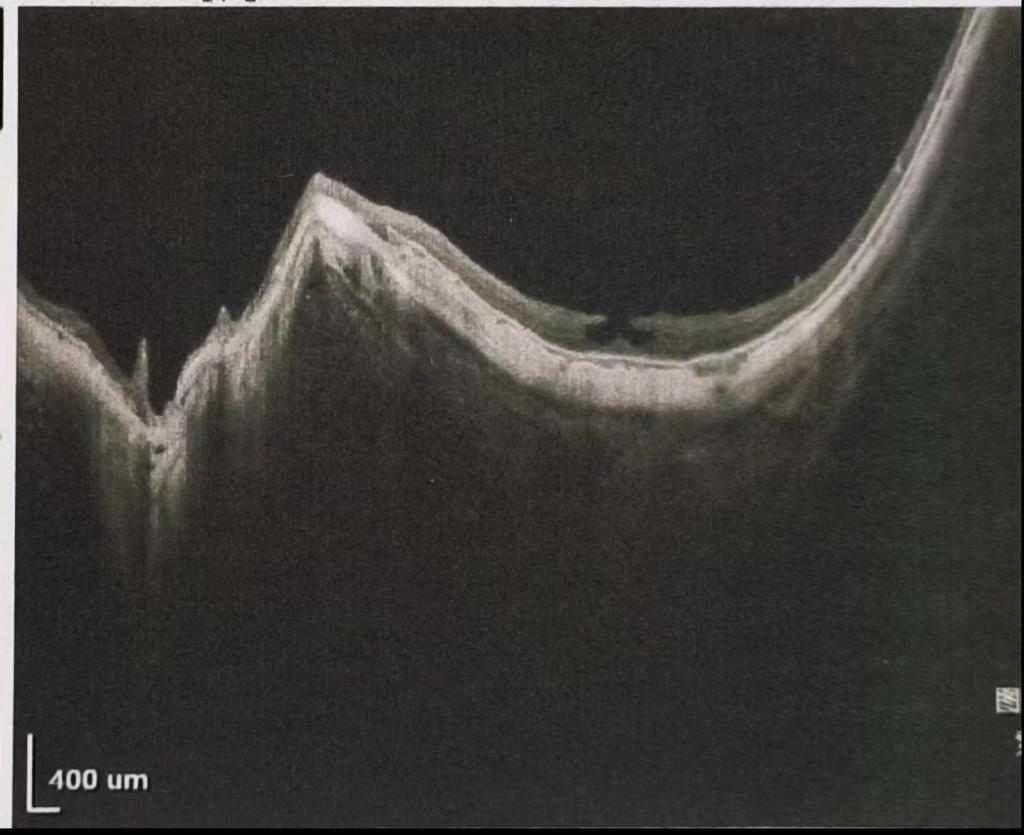

超高度近视指近视度数超过900度,这部分人群占近视患者5%~10%,因为眼轴的过长、巩膜葡萄肿的存在、眼底黄斑病变等眼球本身结构的异常,在手术风险及术中术后并发症均比正常患者要高出很多。比如由于眼轴过长,悬韧带松弛甚至断裂,术中前房浪涌等,会引起后囊破裂,玻璃体脱出,重者甚至继发视网膜脱离。因此这类手术属于高难度眼科手术,对术者的手术水平、术中应变能力都有很高的要求。对于手术团队的管理能力是极大的考验。此患者眼轴超长,属于比较罕见的眼轴长度。术前眼科白内障专业团队对患者进行了仔细检查,在眼科柏凌主任主持科室进行了术前讨论,制定了详细的术前术中风险预案,保证了最后手术的顺利实施。